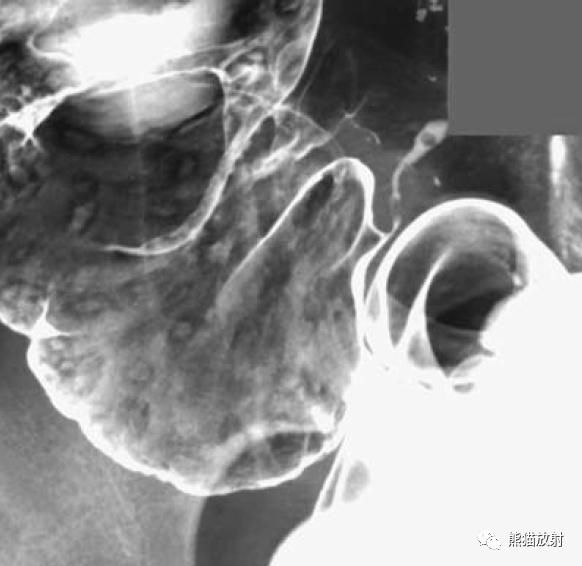

结肠腺癌。肠壁环形增厚,苹果核征;可见溃疡形成(箭)。

直肠远端癌(小箭),呈弥漫性地毯样浸润。息肉状浸润性直肠癌(大箭)。